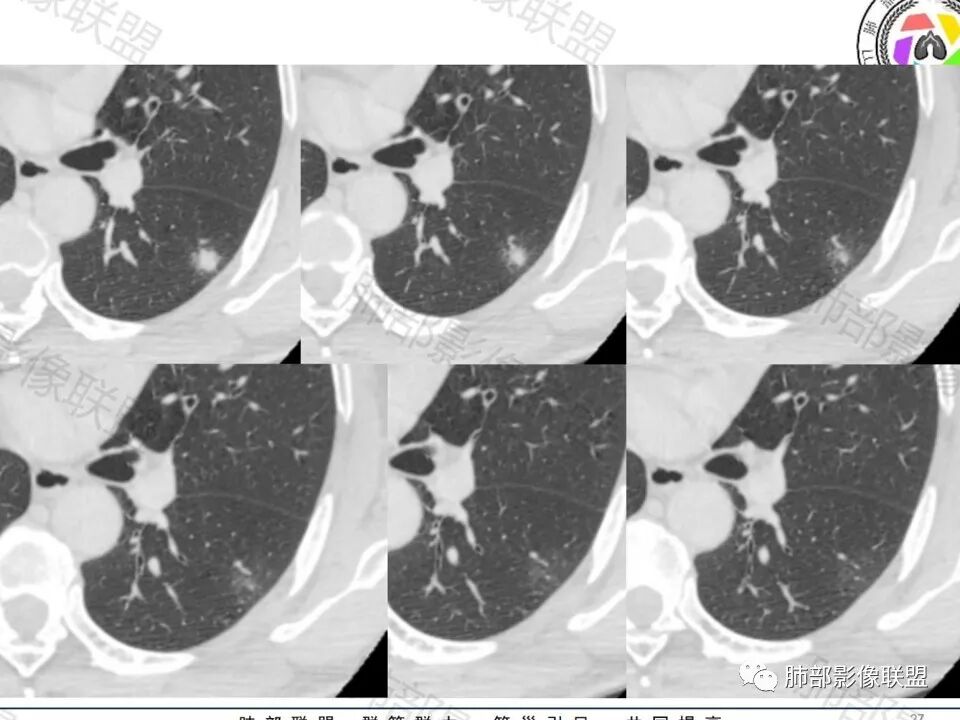

玫:

男,60体检发现左肺下叶结节,左肺下叶类圆形结节影,边界清晰,边缘见浅分叶及细短毛刺,病灶内见增粗血管影穿行,相应层面胸膜增厚,双肺另见微小结节影,增强扫描病灶轻度强化,考虑隐球菌,除外腺癌。

老年男性,左肺下叶背段胸膜下孤立结节,整体圆顿,周围有晕,晕中毛刺,似乎支持隐球,但边缘有一囊腔,恶性不能除外!等答案!

穿越七海的风:

左肺下叶胸膜下类圆形结节,无分叶,无胸膜牵拉,周围有晕,血管支气管进入,考虑隐球菌

左肺下叶胸膜下实性小结节,边缘可见毛刺,轻度收缩,近端与血管束相连,远端轻度牵拉胸膜,并远端可见小空泡,平扫密度均匀,增强后渐近性强化,考虑腺癌,鉴别隐球菌

老年男性,CT左肺下叶胸膜下类圆形结节,边缘光滑,无分叶,可见毛刺,相邻胸膜多条牵拉,局部胸膜增厚,(多见炎性病变),病灶周围可见模糊晕征,血管支气管进入,考虑隐球菌,现实中万万不能排除肺癌。

许慧良:

中老年男性患者,无症状体检发现,胸部CT:左下肺内前基底段近胸膜下类圆形结节,边缘清晰,周围晕征,周围毛刺细软,有胸膜牵拉及血管进入,增强扫描明显不均匀强化,考虑炎性肉芽肿,隐球菌可能,鉴别腺癌

类圆形,边缘稍平直,周围晕中细微毛刺,密度均匀,均匀强化,血管走形自然,稍牵拉扭曲,支气管在近端堵塞